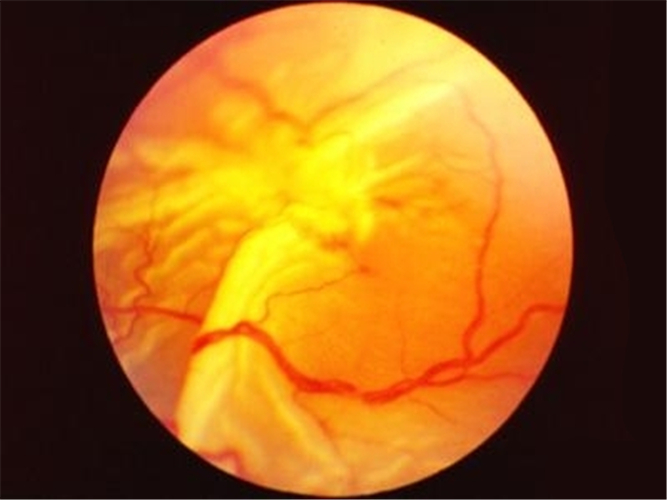

嚴重視網膜脫落

嚴重的視網膜脫落